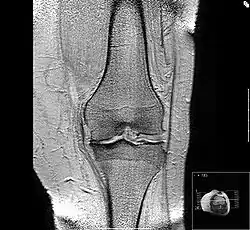

Diagnosis is made with reasonable certainty based on history and clinical examination.[52][53] X-rays may confirm the diagnosis. The typical changes seen on X-ray include: joint space narrowing, subchondral sclerosis (increased bone formation around the joint), subchondral cyst formation, and osteophytes.[54] Plain films may not correlate with the findings on physical examination or with the degree of pain.[55]

MRI of osteoarthritis in the knee, with characteristic narrowing of the joint space -